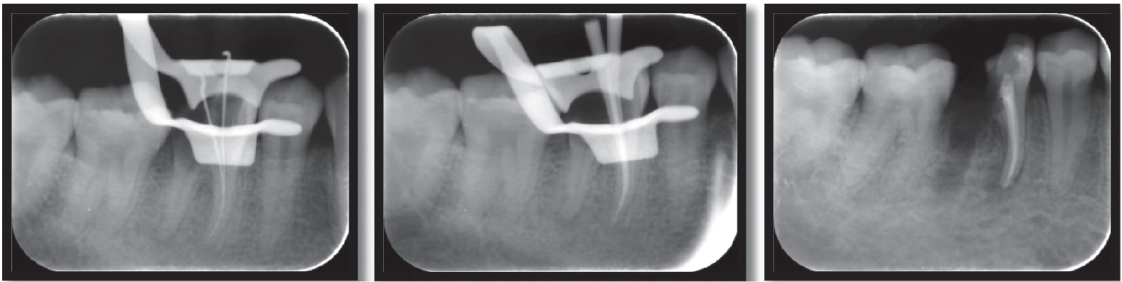

Figure 3. Steps of root canal treatment

thumb